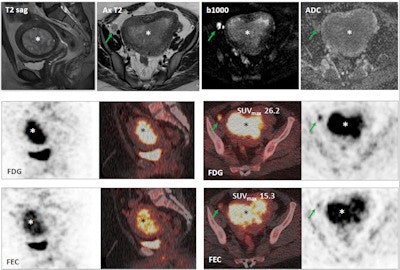

Images show a 29-year-old woman with stage IB grade 2 endometrioid adenocarcinoma filling the endometrial cavity (asterisks). There is intense uptake with FDG (26.2) and FEC (15.3). There is a lymph node (arrows), which shows on T2-weighted DWI (top row), as well as FDG-PET/CT (middle row) and FEC-PET/CT (bottom row). Images courtesy of Dr. Tara Barwick.

DWI was performed on a 1.5-tesla system with a torso phased-array coil. The FDG-PET/CT imaging protocol included a scan from the upper thighs to the skull base after four to six hours of fasting and FDG uptake of 60 minutes. The FEC-PET/CT exam was the same protocol as FDG-PET/CT and included the administration of 200 to 300 MBq of FEC.

Researchers then correlated information on tumor grade, primary tumor FDG maximum standardized uptake values (SUVmax), FEC SUVmax, and the apparent diffusion coefficient (ADC) mean for DWI. Histology was used as the reference standard.

Among the 11 patients, the mean FEC SUVmax was 7.2 (± 3.8), which was significantly lower than the FDG SUVmax of 16.6 (± 10.7).

The researchers found, however, positive correlation between FEC SUVmax and FDG SUVmax (r = 0.78), but no correlation between ADCmean and FEC or FDG SUVmax (r = -0.35 and -0.24, respectively).